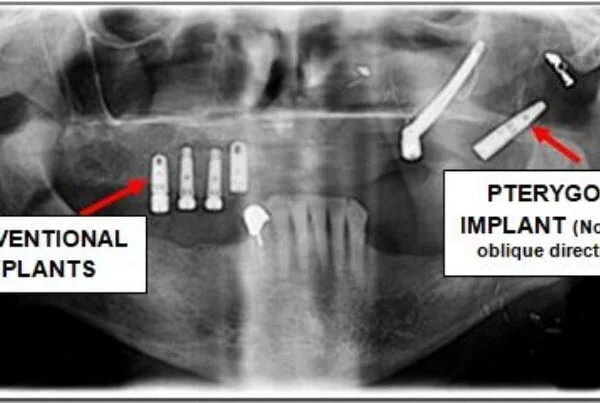

Implanty skrzydłowe to wysoce specjalistyczne, znacznie dłuższe implanty tytanowe, których protokół chirurgiczny opiera się na zupełnie innej filozofii. Zamiast wkręcać je w cienką, zanikłą kość dokładnie w miejscu brakujących zębów, doświadczony chirurg szczękowo-twarzowy wprowadza je pod ściśle określonym kątem, w sposób całkowicie omijający pustą przestrzeń zatoki szczękowej.

Gdzie w takim razie te implanty są zakotwiczone, skoro brakuje kości szczęki? Implant trafia znacznie głębiej, w tak zwany wyrostek skrzydłowaty kości klinowej (łac. processus pterygoideus). Jest to obszar o niezwykłej gęstości – bardzo twarda, zbijona struktura kostna zlokalizowana w głębi czaszki. Co najważniejsze z punktu widzenia pacjenta: ta kość nigdy nie ulega zanikowi, niezależnie od tego, jak dawno straciłeś swoje naturalne zęby.